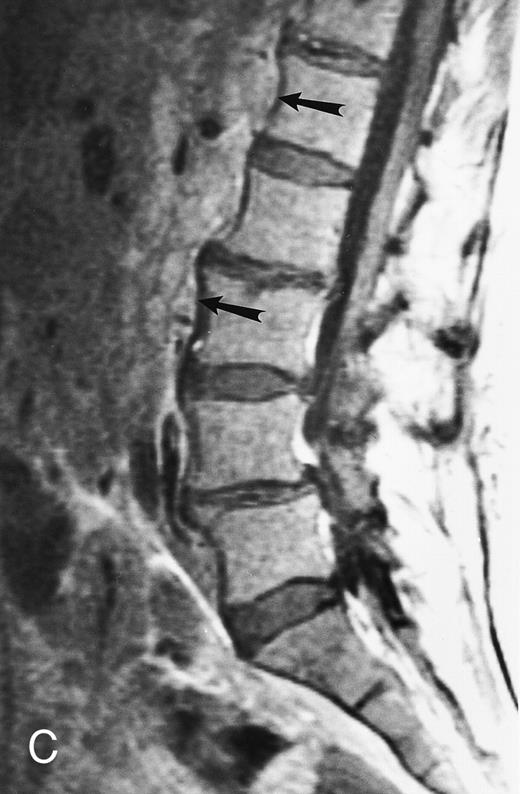

Diffuse MR pattern of abnormal marrow in a 29-year-old man with AML: T1-weighted sagittal (500/10, TR/TE) (A), T2-weighted, fat-suppressed fast spin echo sagittal (5000/96, TR/TE, ET 16) (B), and enhanced T1-weighted sagittal (500/10, TR/TE) (C) MR images of the thoracic spine. The abnormal vertebral bodies in (A) are dark and isointense to the intervertebral discs and in (B) they become bright. In (C), the abnormal marrow enhances and the vertebrae become brighter than the discs. Note extraosseous mass (arrowheads) in the posterior epidural space with preservation of the bony cortex.